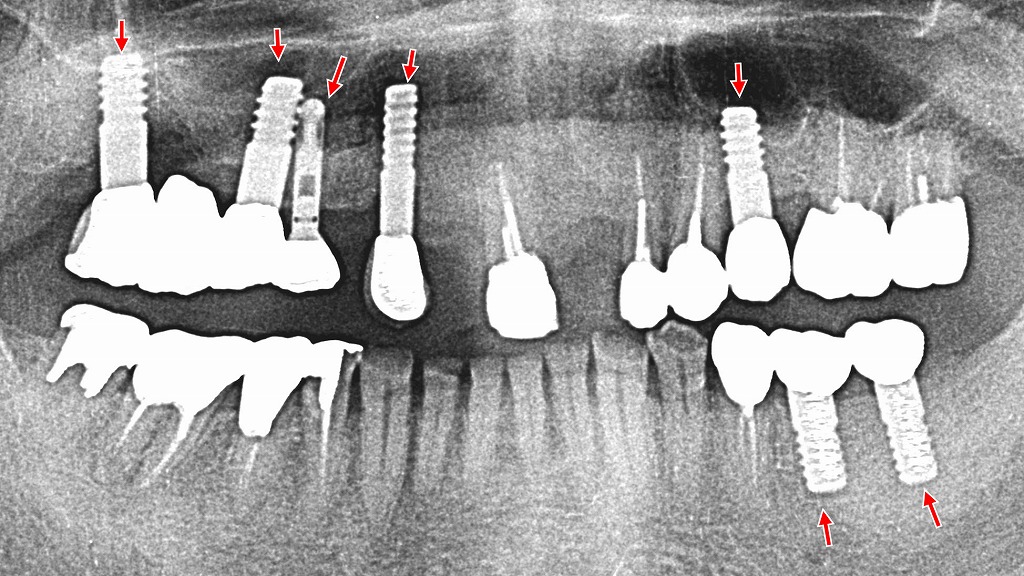

🦴インプラントや外科処置時の応用

浸潤麻酔は、インプラント埋入や軽度の外科処置(小手術)にも活用されます。特に顎の骨に近い部位や粘膜切開を伴う処置において、骨膜や周囲組織に対してしっかりと浸潤させることで、痛みをコントロールできます。

例:

- インプラント手術

- 歯根端切除術

- 歯ぐきの切除や形成(歯周外科)

- 小帯切除術

ただし、広範囲の麻酔が必要な場合は、伝達麻酔が必要となることもあります。